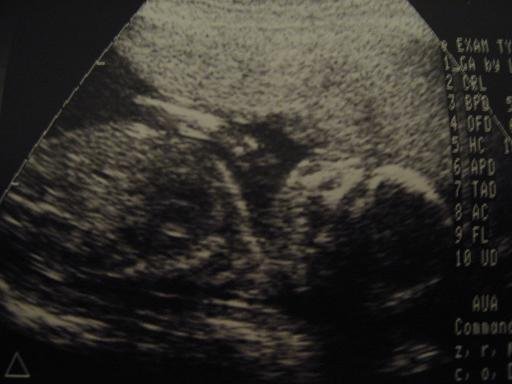

18. heti genetikai uh eredménye (10.22.)

BPD: 46

HC: 175

AC: 151

FL: 29

Ép koponya konfiguratio, agykamrák norm.tágasságúak. Arckoponya: eltérés nélkül.

Gerincoszlop követhető, csigolyaívek zártak, megtartottak.

Szív: 4 üregű, billentyűk ábrázolódnak.

Gyomor és hólyatelődés látható. A vesék üregrendszere norm. tágasságú.

Végtagok csöves csontjai jól ábrázolódnak, épek.

Placenta: mellső falon, középső részén, a méhűr felé cystikus. /28X14mm/

Köldökzsinórban 3 ér.

Magzatvíz mennyisége: átl.

A MSzNUT érvényben lévő protokollja szerint végzett vizsgálat során magzati rendellenesség nem észlelhető.

Vélemény: a mért értékek 19 hetes 6 napos graviditásnak felelnek meg.

A vizsgálat szerint a pocaklakóm legény!:)